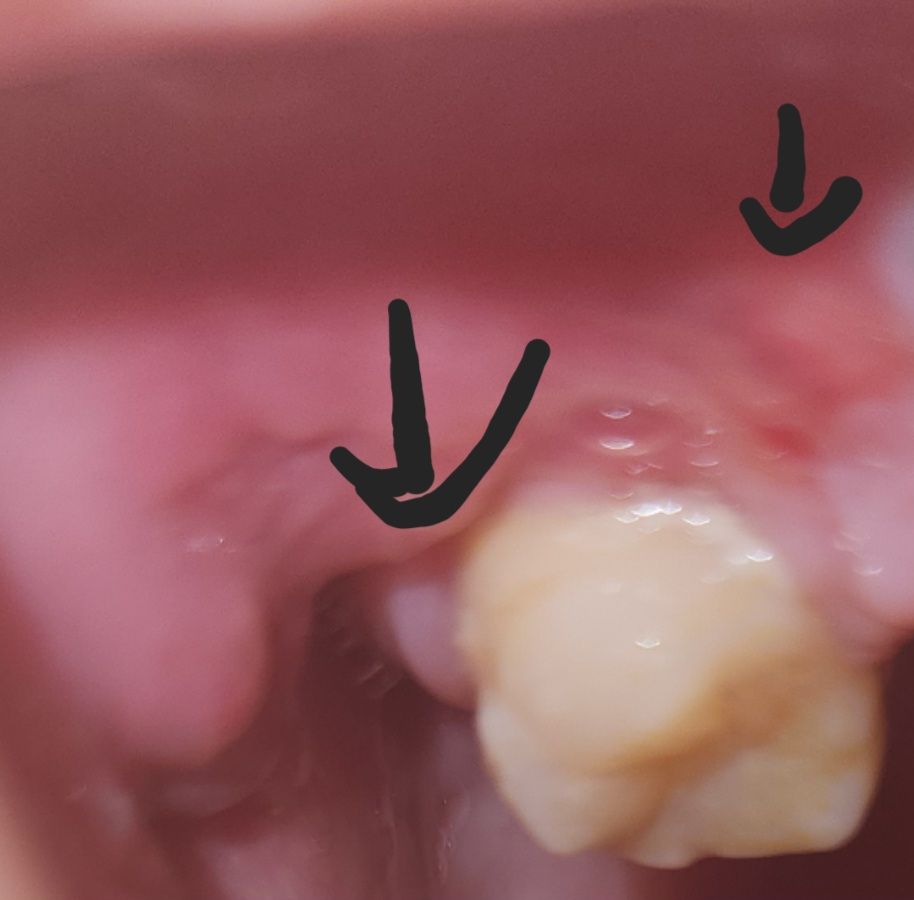

잇몸에 혹 생겼는데 괜찮을까요~???

잇몸에 혹? 비슷한게 생겼는데 혹시 괜찮나 싶어서요

구강내의 단순 연조직이 증식된것일수도 있고 염증에 의한 것일수도 있습니다.

크게 문제가 잇는건 아니고 잇몸이 낫는 과정에서 잇몸이 약간 과증식되서 그런거니 너무 걱정하지 않으셔도 됩니다.

우선 이 혹이 통증도 없는 경우 우선 지켜보길 권하며, 만약 통증이 수반되는 경우 잇몸농양일 가능성이 많습니다.